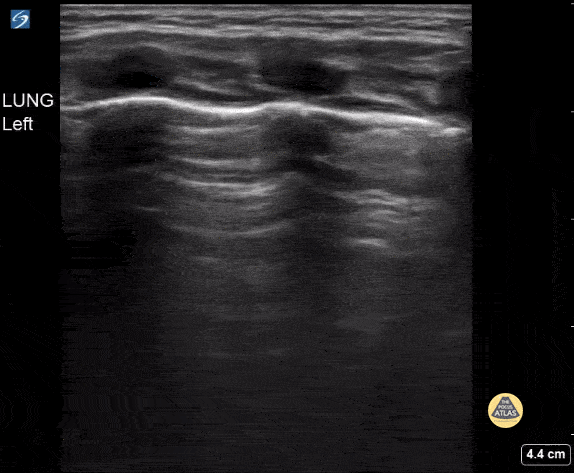

9 month old with respiratory distress. Diffuse confluent B lines found on POCUS consistent with bronchiolitis. Contributor: Kathryn Pade, MD, Rady Children's Hospital San Diego